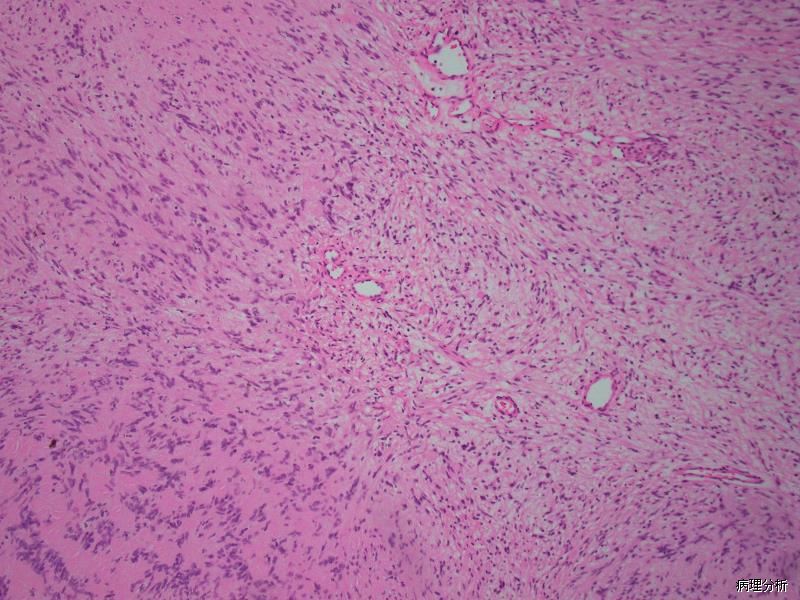

3. 镜下典型特征是由交替性分布的 Antoni A 区和 Antoni B 区交替分布组成,两区的比例因病例不同而异,两区之间可有移行,也可界限分明;

4. Antoni A 区由短束状平行排列的梭形施万细胞组成,也称束状区,细胞胞质丰富、淡嗜伊红色,胞界不清,常见栅栏状排列;部分病例可见瘤细胞排列成洋葱皮样或漩涡状结构,或形成 Verocav 小体样结构;

5. Antoni B 区,由排列疏松、零乱的星芒状施万细胞组成,也称网状区,可有微囊形成;细胞核常圆形或卵圆形,深染,有时可见核内假包涵体;部分病例可见大而不规则的血管,管腔内常见血栓,管壁厚,多伴有程度不一的胶原变性,有时在血管周围可见含铁血黄素性沉着及灶性的泡沫样组织细胞反应;